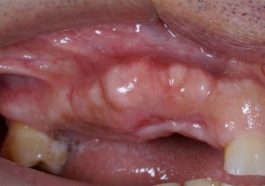

eksostosis tulang

Eksostosis Tulang: Penghalang dalam Pemasangan Gigi Palsu